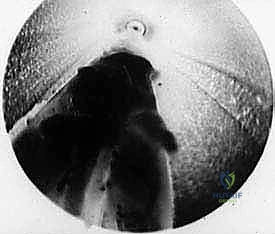

TECH FIG 6 • C. Endoscopic view of knife blade transecting the transverse intermetatarsal ligament.

TECH FIG 6 • D. Endoscopic view after release of transverse intermetatarsal ligament.